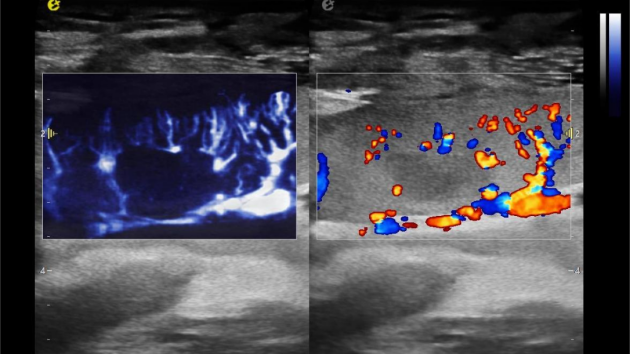

微米级超高分辨率血流信号显像

在肾移植领域,医生最怕的不是手术刀下的惊心动魄,而是那些手术后肉眼看不见的危机——急性排斥反应导致的血小板聚集形成的微血栓、毛细血管网损伤等...这些“隐形杀手”曾让无数移植肾在悄无声息中衰竭。而hjc888黄金城官网医疗(ESI)的iPlane Vascular平面波超微细血流显像技术,正是为破解这一难题而生。

1) 基于OmniSound?平面波超快速平台,超声信号采集帧频提高了200倍(25000Hz)。

2) 可检测20-50μm级细小血管低速血流信号,能看清头发丝1/2粗细的微血管;

这一项无创、无辐射操作简便且无需造影剂的黑科技,相当于用"高速摄像机"记录血液细胞的运动轨迹,让血管并发症"无处遁形。